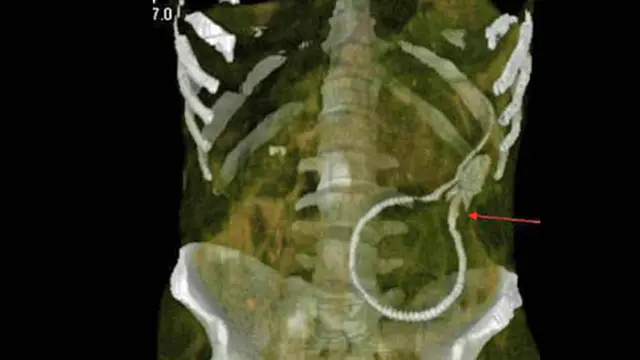

Pria Telan 830 Gram Pil Narkoba

Gambar di atas tampak mengerikan, itu adalah 72 kapsul kokain berukuran besar yang ada di dalam tubuh seorang pria. Semua kapsul itu adalah obat-obatan terlarang dengan berat mencapai 830 gram. Tidak terbayang bagaimana rasanya memiliki tubuh berisi puluhan kapsul seperti gambar di atas.

Gambar ini diambil dari alat pemindai CAT oleh Polisi Federal Brasil. Pada tanggal 16 September 2011, seorang pria muda yang diidentifikasikan sebagai pria Irlandia mencoba naik pesawat di bandara Congonhas di Sao Paulo, Brasil. Agar tidak ketahuan membawa narkoba, pria ini nekat menelan 72 pil. Akibatnya.. dia berurusan dengan polisi dan seperti itulah bagian dalam tubuhnya. Hii..